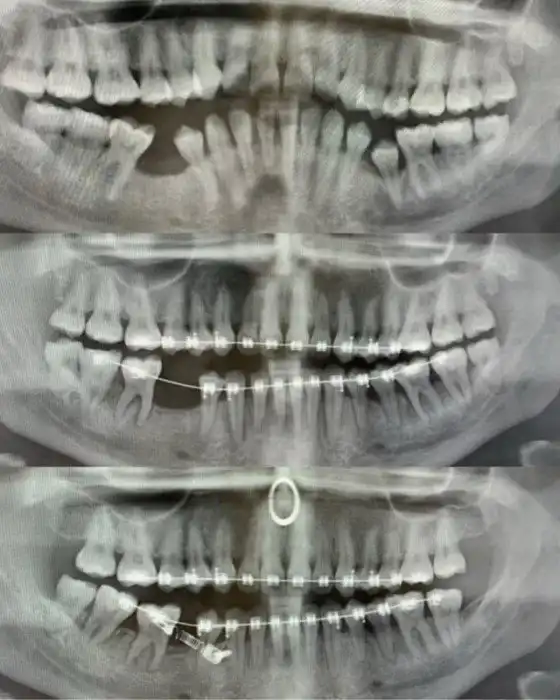

14. «Мои зубы до брекетов и после»